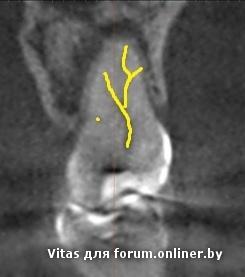

по кт этот "типа срез" начинает место в медиально-щечном канале и уходит почти горизонтально в небный канал....

красным отмечен канал, который был найден и обработан, желтым - пропущенный

ЗЫ: Каналы не сливались в вашей ситуации. в канале был живой нерв, выход был отдельный, в эндодонтии главное обтурировать апикальные 3-5 мм!

Мыслить нужно глобальнее, на снимке и вот так можно расмотреть.